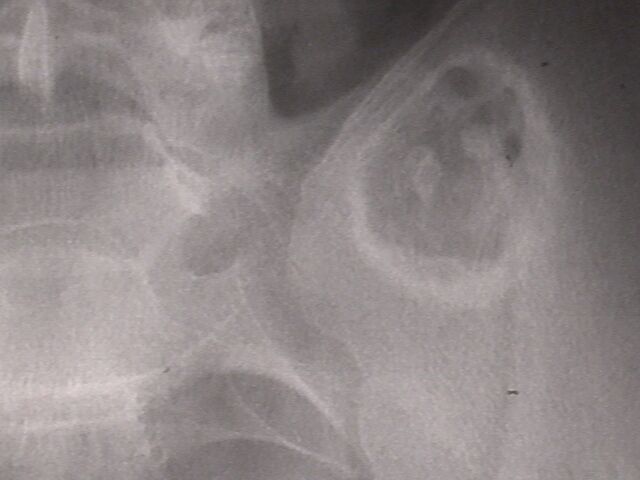

У сына ( 18 лет) медицинской сестры, во время обследования в военкомате на рентгенограмме выявлена опухолевидное образование, клинически бессимптомное.

Больной консультирован в Новосибирском онкологическом диспансере, областной консультативной поликлинике. Поставлен диагнозэнхондрома левой подвздошной кости. Рекомендовано наблюдение контрольное рентгенологическое обследование через год. По-моему лучше бы опухоль назвать экхондромой (рост преимущественный вне кости). Считаю, что лучше предложить оперативное лечение- удаление опухоли Прошу коллег высказать свое мнение. Если необходимо оперативное лечение - где можно его осуществить.

Посмотрели с коллегой из ортопедического отделения, где как раз доброкачественными опухолями скелета занимаются. Желательно бы

дообследовать пациента - уточнить на КТ форму, размеры и локализацию, показать опытным рентгенологам. Как-то странновато образование

пересекает крестцово-подвздошный сустав.